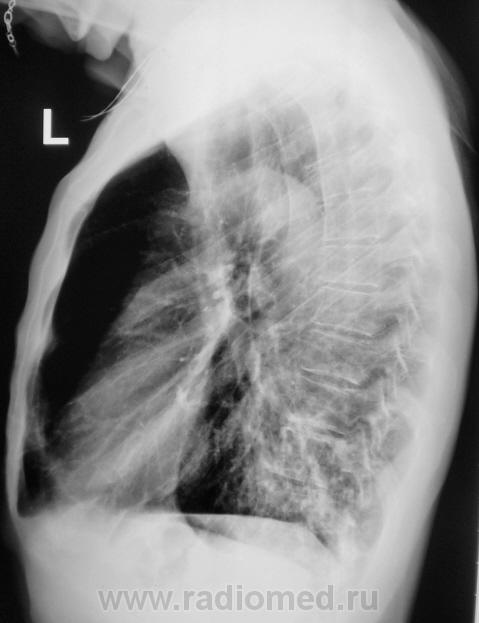

Пациент направлен на рентгенографию ОГК с диагнозом  - "Левостороняя пневмония".

Анамнез стандартный. Ранее неоднократно страдал обострениями хронического бронхита. Сейчас вот не нашутку занемог - температура до 38, откашливает мокроту, кашель продуктивный.

Диагноз левосторонней нижнедолевой С10, С9 сементарной пневмонии наверное будет верным, а с учётом фона- с наличием бронхоэктазов.